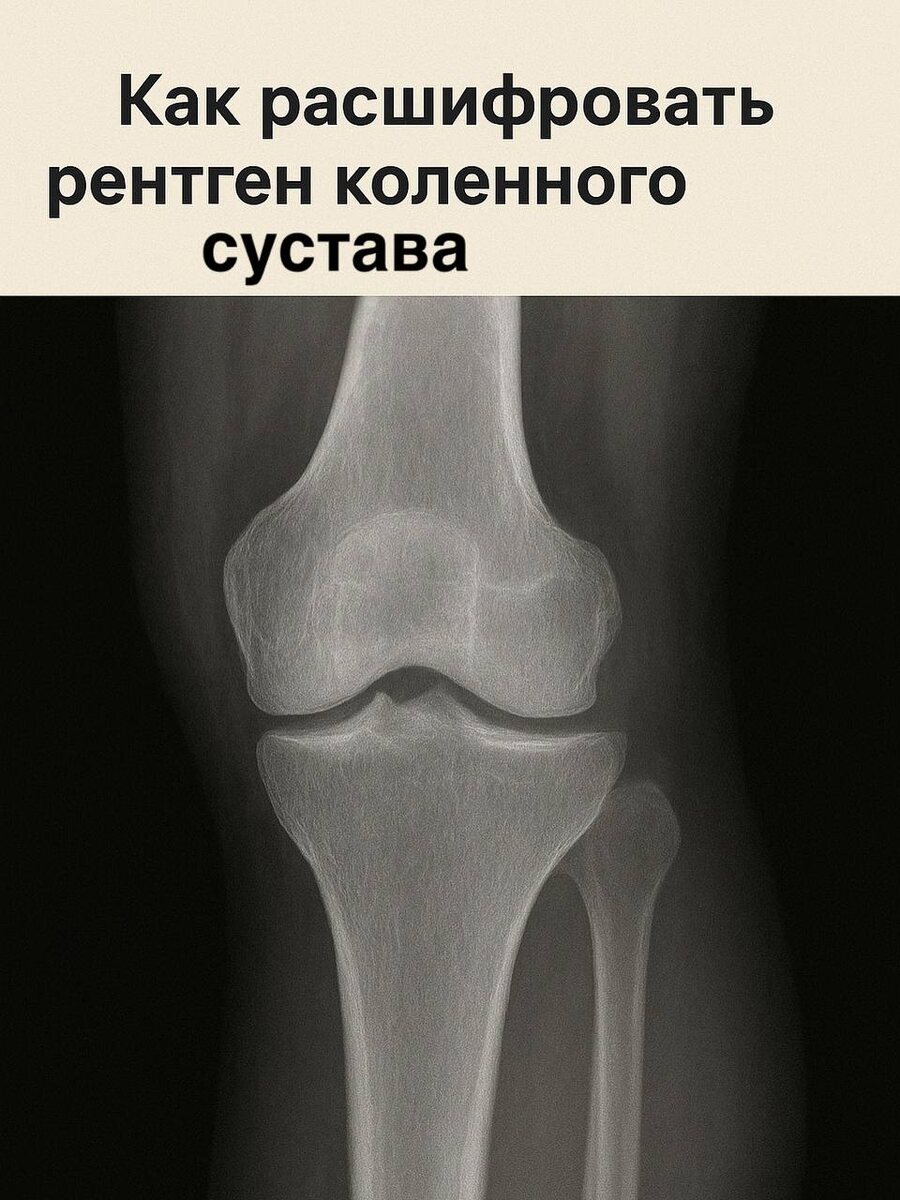

🦵 Как расшифровать рентген коленного сустава

🦵 Как расшифровать рентген коленного сустава Получили снимок, а в заключении непонятные слова? Разберём, что значит каждый термин 👇 📌 1. Суставная щель Это расстояние между костями. Сужена — признак артроза (износ хряща). Расширена — бывает при воспалении или скоплении жидкости. 📌 2. Костные разрастания (остеофиты) Выступы по краям костей — частый спутник артроза. Они ограничивают подвижность и вызывают боль. 📌 3. Субхондральный склероз Уплотнение костной ткани под хрящом. Это ответ организма на повышенную нагрузку. 📌 4. Суставная поверхность В норме — ровная. Если видны неровности или деформации — процесс зашёл далеко. 📌 5. Мягкие ткани и выпот Если врач пишет «выпот в суставе» — значит, есть жидкость, часто при воспалении или травме. 💡 Важно: рентген показывает только кости. Хрящи, связки и мениски лучше видно на МРТ. Если хотите точно понять, насколько поврежден сустав — не делайте выводы сами, покажите снимок врачу-рентгенологу или ортопеду. #рентген #коленосустав #артроз